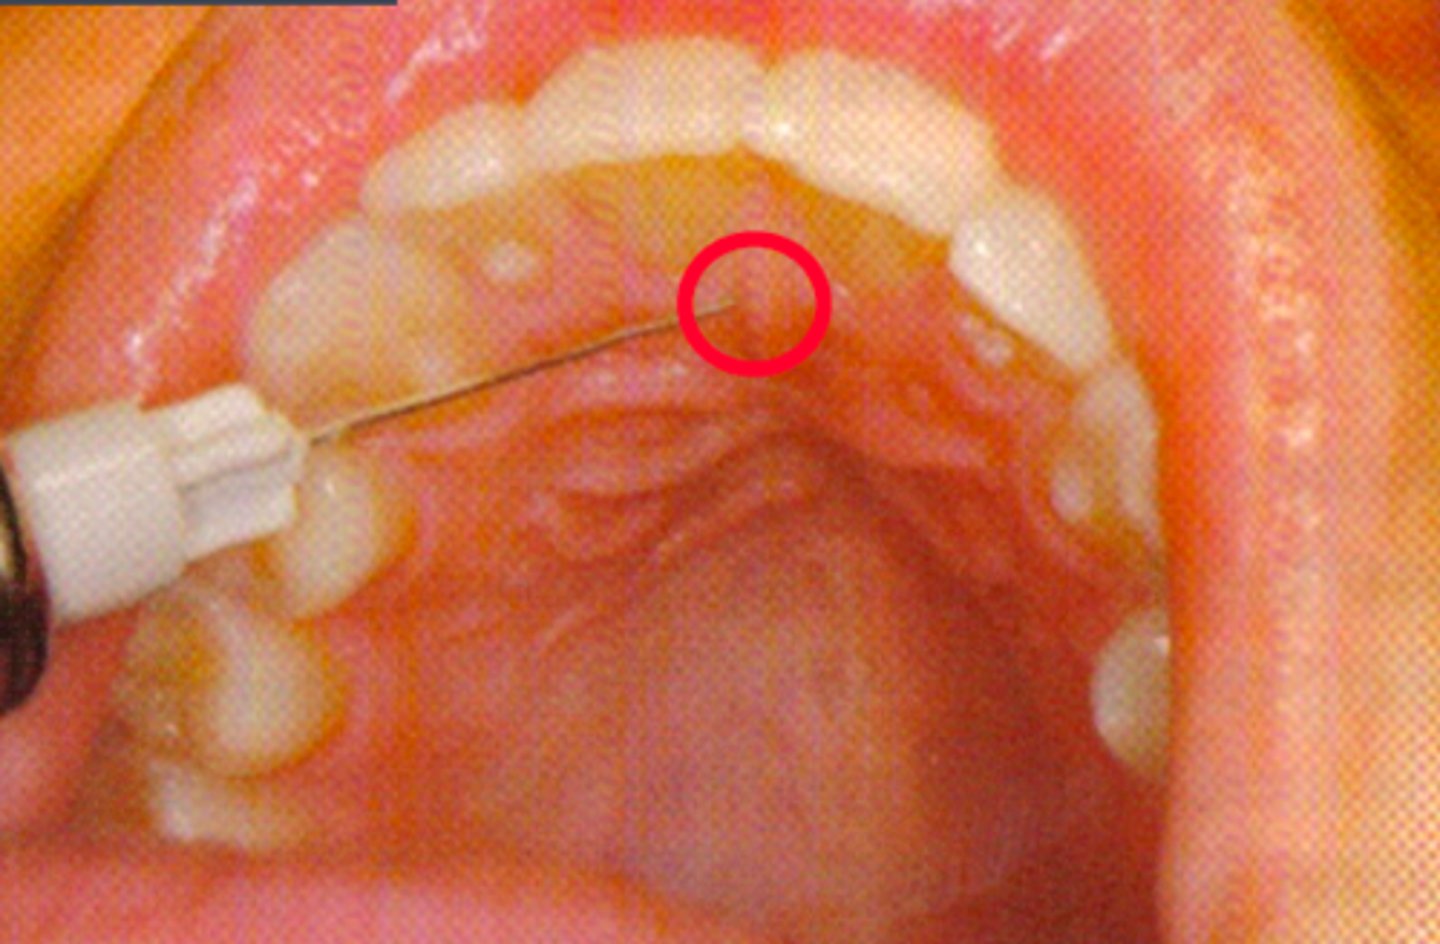

Nasopalatine Nerve Block (single injection)

ID the anesthesia technique:

Nasopalatine Nerve Block (multiple injections) #2

Palatal mucosa to the lateral border of the incisive papilla

what is the insertion point for a Nasopalatine Nerve Block (single injection technique)?

1st injection: labial frenum

2nd injection: interdental papilla between central incisors

3rd injection: incisive papilla (nasopalatine nerve block)

what is the insertion point for a Nasopalatine Nerve Block (multiple injection technique)?

Approach the injection site at a 45 degree angel toward the incisive papilla

what is the insertion path for a Nasopalatine Nerve Block?

3 to 5 mm

what is the depth for a Nasopalatine Nerve Block?

0.2 to 0.3 ml

what is the anesthetic volume for a Nasoalatine Nerve Block?

Nasopalatine Nerve Block (general)

This type of nerve block will result in the anesthesia of the palatal gingiva of the six anterior teeth and mucoperiosteum of the anterior third of the hard palate: